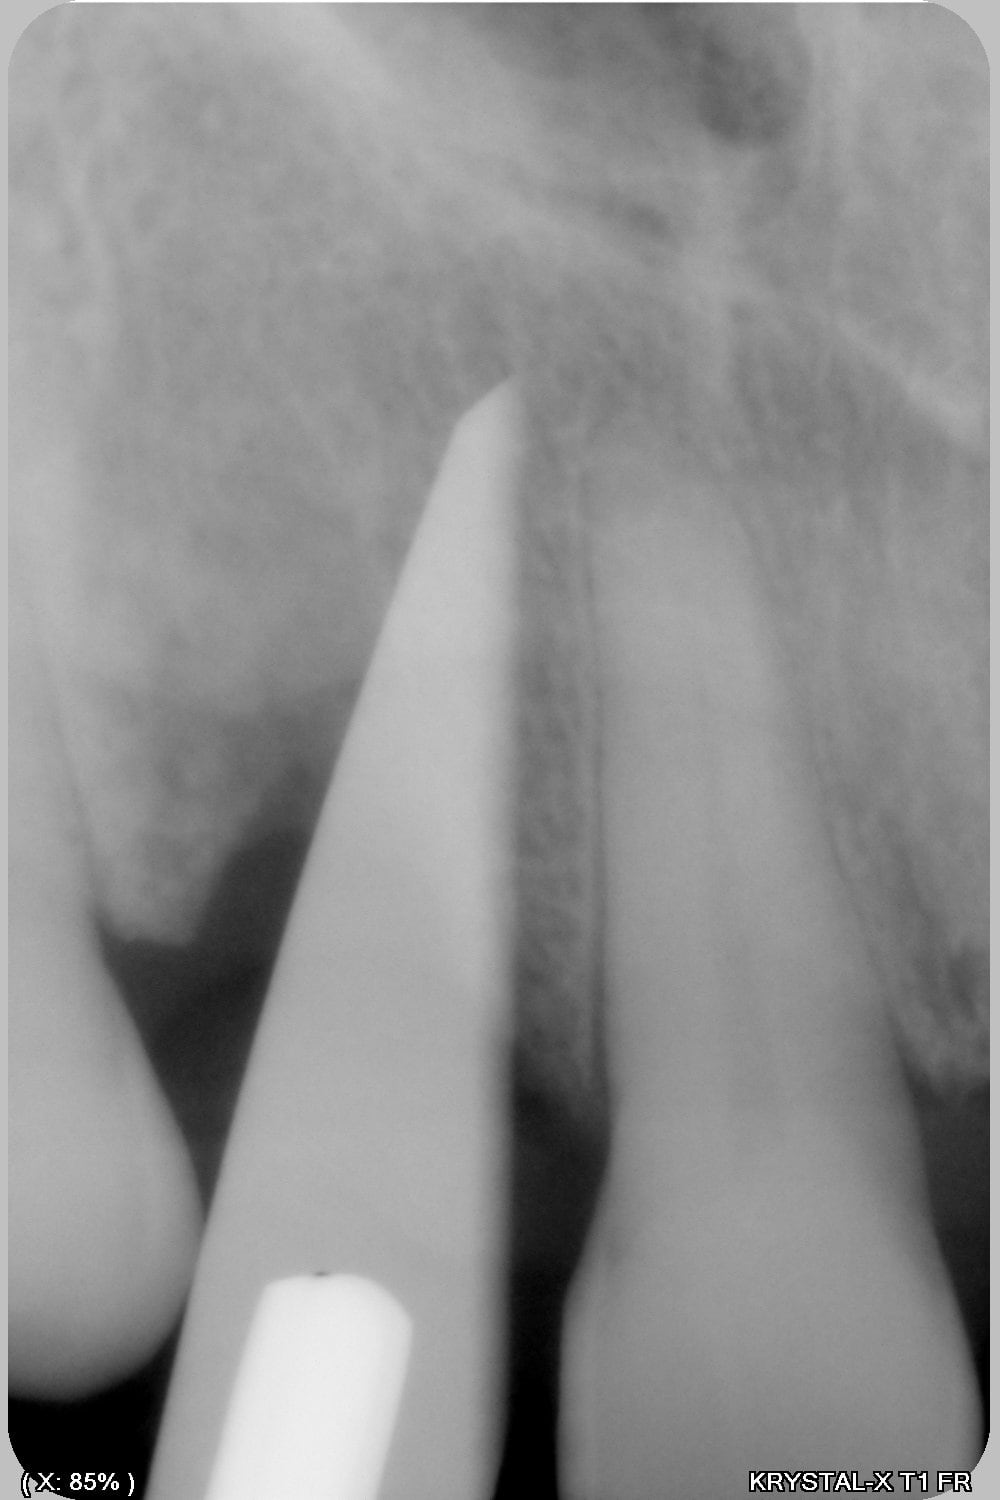

Thomas, tu as un plan pour guider dans un cas comme ça?

ou comment remplacer 12 avec soucis vestibulaire, par un implant, sans greffe, sans ROG, juste avec les mimines....?

vue de l’intérieur..

Et bien pas de cone beam, pas de scanner,pas de panoramique...pour ne pas irradier l'os...et franchement je ne vois pas en quoi un guide me servirait dans un cas comme ça.